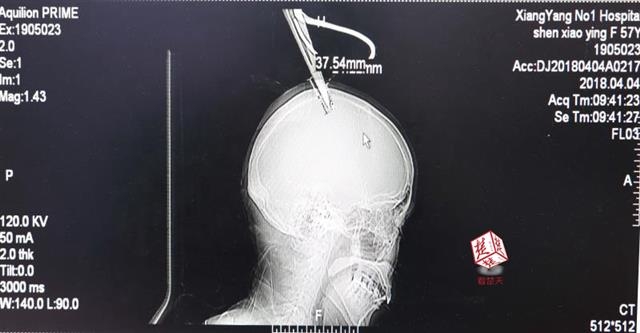

醫(yī)生檢查發(fā)現(xiàn),剪刀刀尖斜嵌在沈某顱骨里,離腦髓只有兩三毫米。所幸是斜著插進(jìn)去,如果是垂直刺入,很有可能造成癱瘓。

4月4日清晨,襄陽(yáng)市樊城區(qū)太平店鎮(zhèn)57歲的農(nóng)村婦女沈某,在采摘香椿嫩芽時(shí),綁在竹桿上的剪刀因竹子腐朽不慎折斷,剪刀斜插入頭顱。經(jīng)過(guò)及時(shí)搶救,目前脫離生命危險(xiǎn)。

醫(yī)生檢查發(fā)現(xiàn),剪刀刀尖斜嵌在沈某顱骨里,離腦髓只有兩三毫米。所幸是斜著插進(jìn)去,如果是垂直刺入,很有可能造成癱瘓。最終經(jīng)過(guò)手術(shù),剪刀被取出,沈某目前仍在ICU進(jìn)一步觀察。